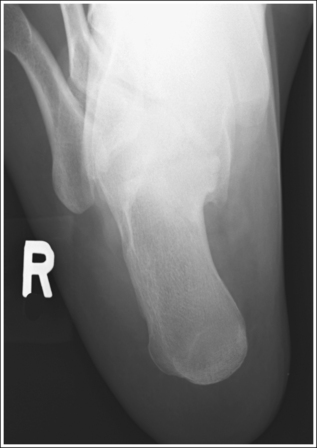

The calcaneus and distal tibia and fibula are in a lateral projection. The domes of the talus are superimposed, the tibiotalar joint space is open, and the distal fibula is superimposed by the posterior half of the distal tibia.

• To obtain a lateral calcaneal projection, begin with the patient in a supine position, with the leg extended (Figure 6-40) and the foot dorsiflexed until its long axis forms a 90-degree angle with the lower leg. Rotate the patient toward the affected leg until the lateral foot surface is against the IR; then, adjust the degree of rotation until the surface is aligned parallel with the IR (Figure 6-41). For most patients, this positioning places the lower leg parallel with the imaging table. If this is not the case, as with a patient with a large upper thigh, the foot and IR should be elevated to place the lower leg parallel with the imaging table.

• Talar domes: The domes of the talus are formed by the most medial and lateral aspects of the talar's trochlear surface. They are visible on a lateral calcaneal projection as domed structures that articulate with the tibia. When a lateral calcaneus projection has been obtained, the talar domes should be superimposed and appear as one, and the tibiotalar joint should be open. If the lateral calcaneus is mispositioned, the domes are individually demonstrated and obscure the tibiotalar joint. Misalignment of the domes will result from poor knee and foot positioning.

• Effect of lower leg positioning on talar dome superimposition. Often, if the knee is not fully extended (Figure 6-42) or if the distal tibia is not elevated to place the lower leg parallel with the IR (in a patient with a large upper thigh), the proximal tibia is positioned farther from the imaging table than the distal tibia. The resulting image demonstrates the lateral talar dome proximal to the medial talar dome, and the height of the longitudinal arch appears less than it actually is because the cuboid shifts anteriorly and the navicular bone moves posteriorly in this position; the talocalcaneal joint will be narrowed (see Image 27). If the distal tibia is positioned farther from the imaging table than the proximal tibia, the medial talar dome is demonstrated proximal to the lateral dome, and the height of the longitudinal arch appears higher than it actually is because the cuboid shifts posteriorly, the navicular bone moves anteriorly, and the talocalcaneal joint will be wider (see Image 28).

The long axis of the foot is positioned at a 90-degree angle with the lower leg.

• In most cases, when a patient is relaxed, the foot rests in plantar flexion, making it difficult for the patient to maintain a lateral position. Often, the patient rotates the foot too far anteriorly, elevating the heel and rotating the foot (see Image 31). Consequently, it is best to dorsiflex the patient's foot, placing its long axis at a 90-degree angle with the lower leg.

The midcalcaneus is at the center of the exposure field. The tibiotalar joint, talus, calcaneus, and calcaneus-articulating tarsal bones are included within the collimated field.

• Center a perpendicular central ray 1 inch (2.5 cm) distal to the medial malleolus to place the calcaneus in the center of the exposure field. Centering to the midcalcaneus better demonstrates the calcaneus and the surrounding calcaneotarsal and talocalcaneal articulations, allowing for accurate calcaneal inclination measurements and for visualization of calcaneal tuberosity displacement.

• Open the longitudinal collimation enough to include the calcaneus and tibiotalar joint, which is located at the level of the palpable medial malleolus. Including the tibiotalar joint on all lateral calcaneal projections provides a method of judging rotation and determining how to reposition when a rotated lateral calcaneal projection has been obtained. Transverse collimation should be to the calcaneal tuberosity and the calcaneotarsal joint spaces. Ensure that the calcaneotarsal joint spaces are included by extending the transverse collimation at least 2 inches (5 cm) anterior to the medial malleolus (Figure 6-45).